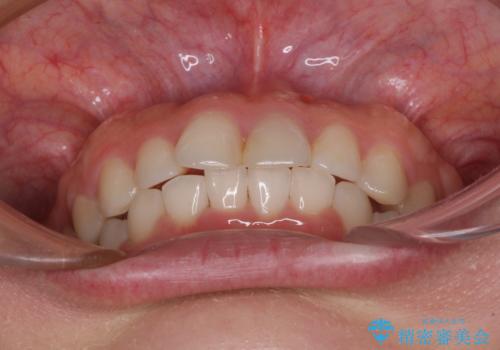

もう少しデコボコを改善したかったのですが、ご本人の希望もあり、装置を除去しました。

後戻りを防止するため、舌側を細いワイヤーによる保定を行いました。